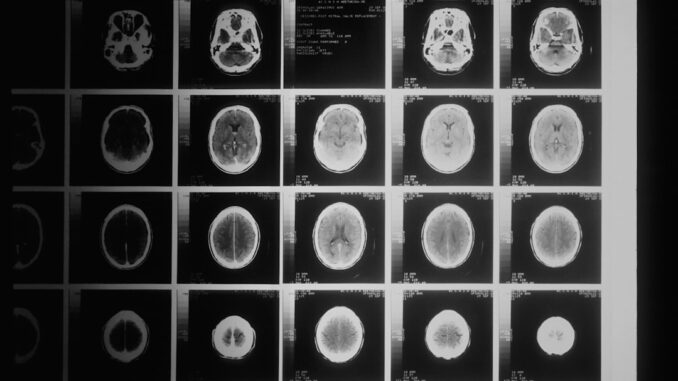

Their focus honed in on various medical imaging modalities, each with its own signature of radiation. We’re talking about the ubiquitous X-rays, which most of us have had at some point, right? Then there are the more potent CT scans, often called CAT scans, which give clinicians incredibly detailed cross-sectional views of the body but deliver a far higher radiation dose. Beyond these, they also considered procedures like fluoroscopy, which uses continuous X-ray beams to visualize moving structures inside the body, and even nuclear medicine scans, involving radioactive tracers. Each of these tools, while invaluable for specific diagnoses, carries a potential cost in terms of ionizing radiation.